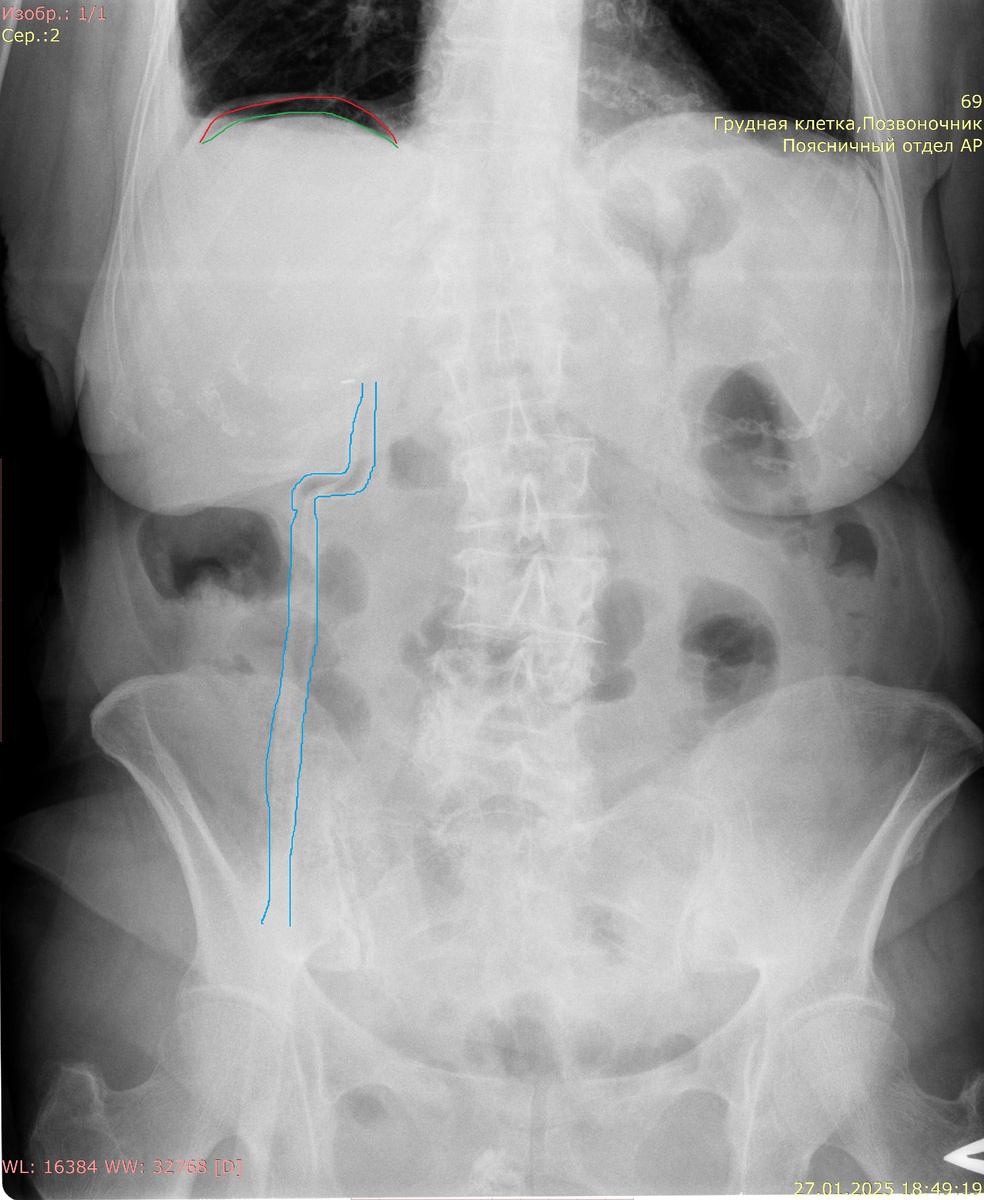

При перфорации полого органа, такого как кишечник или желудок, воздух может накапливаться под диафрагмой, что визуализируется на рентгенограммах в виде пузырьков газа. Эта находка обычно указывает на необходимость неотложной хирургической помощи, так как она может сигнализировать о высокой степени угрозы для жизни пациента. На рентгенологических изображениях свободный газ проявляется как области с пониженной плотностью, чаще всего расположенные под правым или левым куполом диафрагмы. Это связано с анатомическими особенностями расположения органов в брюшной полости, где газ имеет тенденцию подниматься к верхним участкам.

Диафрагма красная, верхний край печени зеленый. Между ними газ - симптом "серпа".